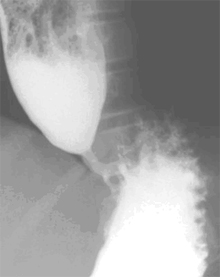

Τα πιο πάνω συμπτώματα είναι χαρακτηριστικά της αχαλασίας και μας κάνουν να υποψιαστούμε την παρουσία της. Η διάγνωση της όμως πρέπει να επιβεβαιωθεί με γαστροσκοπικό και ακτινολογικό έλεγχο και να τεκμηριωθεί με μανομετρία του οισοφάγου, εξέταση που μετρά τις πιέσεις και την κινητικότητα του οργάνου.